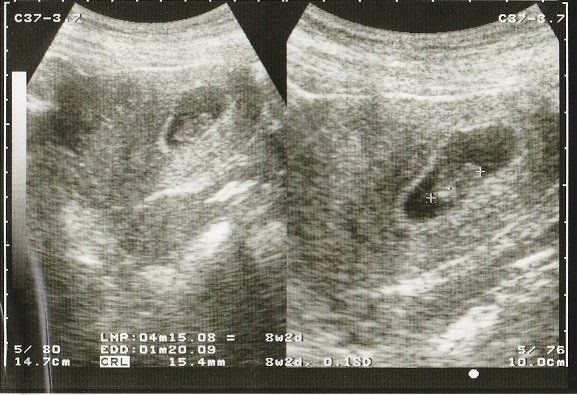

妊娠8週目のエコー写真 10mm以上に成長

CRL(頭殿長=頭からおしりまでの長さ)が10mmを超えました。

順調に大きくなっていますが、まだまだ「大丈夫だろうか?」という不安が大きかった時期。